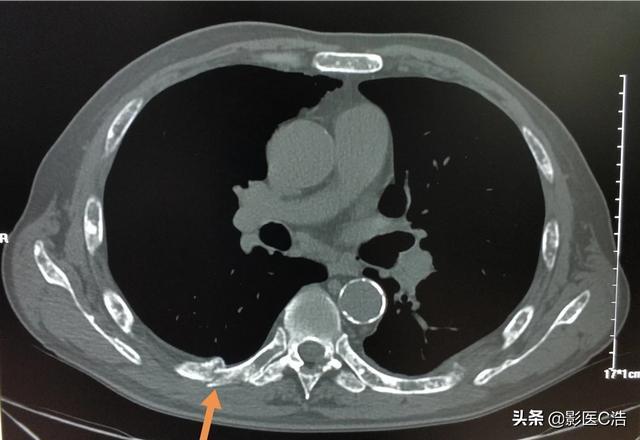

骨転移が骨、一般的には肋骨に発生した場合にも病的骨折が起こることがありますが、これは転移が骨の正常な構造を破壊するため、骨が弱くなり、外力が加わったときに骨折しやすくなるためです。骨転移の中には、骨の周囲に軟部組織の腫瘤として現れるものもありますが、体表には現れないため、発見するのは容易ではありません。病的骨折(下の矢印)

骨に転移しやすいがんがありますが、骨転移の見分け方は?肺がん、肝臓がん、乳がん、前立腺がんなど、がんは転移しやすく、正常な組織を破壊しますが、転移部位として多いのが骨です。私たちの仕事でも、骨の痛みで受診し、検査の結果、がんの骨転移と診断されることがあります。前立腺がんの骨転移(黒丸部分)

癌の骨転移の最も一般的な症状は骨の痛みで、この痛みは緩和されず、徐々に悪化していきます。骨に転移した当初は転移巣が小さいため、周囲の正常組織にはあまり影響がなく、転移部位の骨に少し痛みを感じることもあります。転移が大きくなるにつれて骨の破壊範囲が広がり、周囲の正常な組織や構造(神経、筋肉、筋膜など)も侵されるため、痛みが悪化します。また、転移性腫瘍が大きくなるにつれて、痛みは最初の発作的な痛みから継続的な痛みに発展していきます。つまり、痛みの根本的な原因(正常組織の破壊を引き起こしている転移性腫瘍)が常に存在し、進行しているため、薬用オイルなどを揉むことで痛みが和らぐ通常の痛みとは異なり、後期には痛みを和らげることができません。そのため、進行がんで骨転移の痛みがある患者の多くは、鎮痛のためにモルヒネを使用しなければならないことが多い。